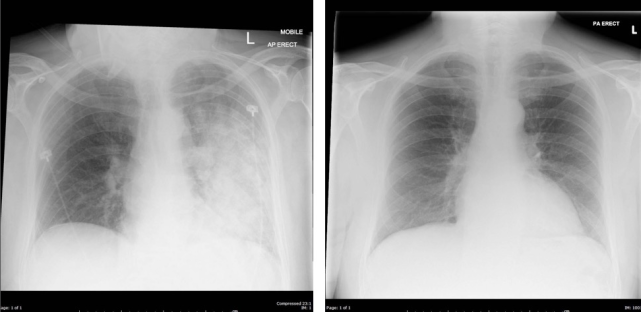

心源性肺水肿